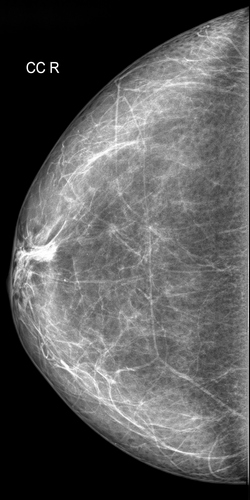

Аномалии молочной железы: медицинские примеры и визуализация

Раздел: Мудрость в деталях